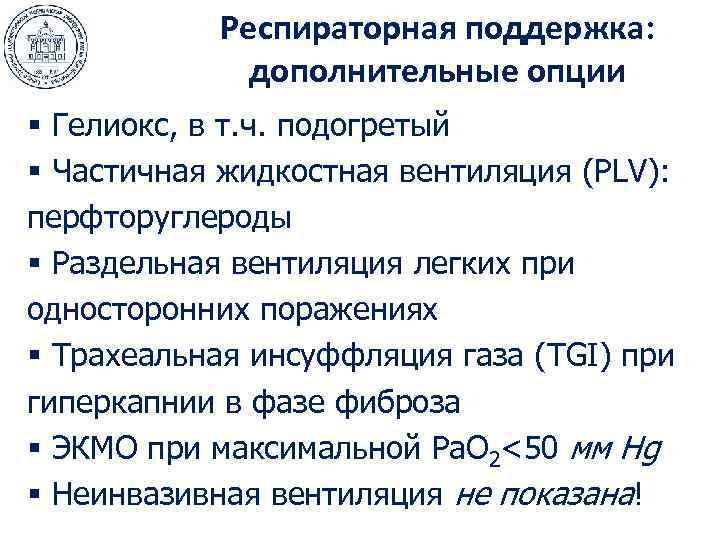

Респираторная поддержка: дополнительные опции § Гелиокс, в т. ч. подогретый § Частичная жидкостная вентиляция (PLV): перфторуглероды § Раздельная вентиляция легких при односторонних поражениях § Трахеальная инсуффляция газа (TGI) при гиперкапнии в фазе фиброза § ЭКМО при максимальной Pa. O 2<50 мм Hg § Неинвазивная вентиляция не показана!

Респираторная поддержка: дополнительные опции § Гелиокс, в т. ч. подогретый § Частичная жидкостная вентиляция (PLV): перфторуглероды § Раздельная вентиляция легких при односторонних поражениях § Трахеальная инсуффляция газа (TGI) при гиперкапнии в фазе фиброза § ЭКМО при максимальной Pa. O 2<50 мм Hg § Неинвазивная вентиляция не показана!